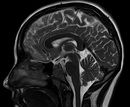

В последнее время наблюдается тенденция к установке большого количества МРТ аппаратов. Но количество специалистов врачей МРТ растет с гораздо меньшей скоростью. Частные клиники вынуждены привлекать к описанию исследований всех подряд, был бы диплом в наличии. Однако в последнее время участилось количество обращений пациентов, недовольных качеством описания МРТ выполненного в коммерческом центре. Самый худший вариант - пациент требует возврата денег, а особо грамотный подает в суд. В итоге медицинский центр терпит значительные убытки. Следует задуматься о содержании такого "неквалифицированного" врача. Налоги и зарплата, социальные выплаты, "хотелки" врача - это не качественно, это я не описываю.... Если посчитать убытки от этого, владельцу можно только прослезиться.

Многие владельцы МРТ центров уже столкнулись с такой картиной. Выход есть, описание дистанционным доктором! И цены радуют глаз, от 250 рублей за исследование! Но, возникает другая проблема, первая и самая главная - как ввести такого доктора в штат? Опять возникают налоги и социальные выплаты. Есть вариант - платить по серой схеме, но здесь есть куча проблем - вывод средств для оплаты, а это дополнительные затраты, плюс ко всему при жалобе пациента - Вам придется объяснить почему стоит подпись человека, который у вас официально не работает. Кроме того, многие так называемые врачи, работающие дистанционно, имеют крайне низкую квалификацию, и их описание МРТ может быть так же абсолютно неверно!

Что же делать владельцу МРТ - центра? Только у Нас есть специальное предложение - все ваши МРТ исследования описывает эксперт по МРТ выступающий на центральном телевидении, обучивший большое количество врачей МРТ, имеющий государственные благодарности. Кандидат медицинских наук, врач Высшей категории Александр Иванчиков. Квалификация врача МРТ крайне важна, некомпетентный врач не в состоянии понять что же с больным и как следствие ставит неверный диагноз, что может привести к инвалидизации и даже смерти! Ваше право требовать описания МРТ исследования только высококвалифицированными врачами. Не идите на поводу у мошенников от медицины, только врачи высшей квалификационной категории и кандидаты медицинских наук с большим опытом практической работы могут поставить верный диагноз. Здоровье ваших пациентов бесценно! А ваша финансовая успешность зависит в первую очередь от ваших пациентов, довольный пациент приведет в ваш центр всех своих знакомых а те своих знакомых. Кроме того, вы можете заключить прямой договор с перечислением за услуги по безналичному расчету, НДС не облагается. Все проблемы серой схемы полностью устраняются. Довольные пациенты, довольный владелец МРТ центра, возрастающая прибыль, цены от 400 рублей за описание одного МРТ исследования врачем высшей квалификационной категории, кандидатом медицинских наук.